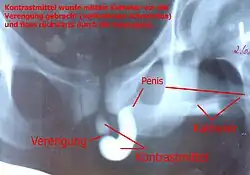

Among ways to diagnose this condition is: